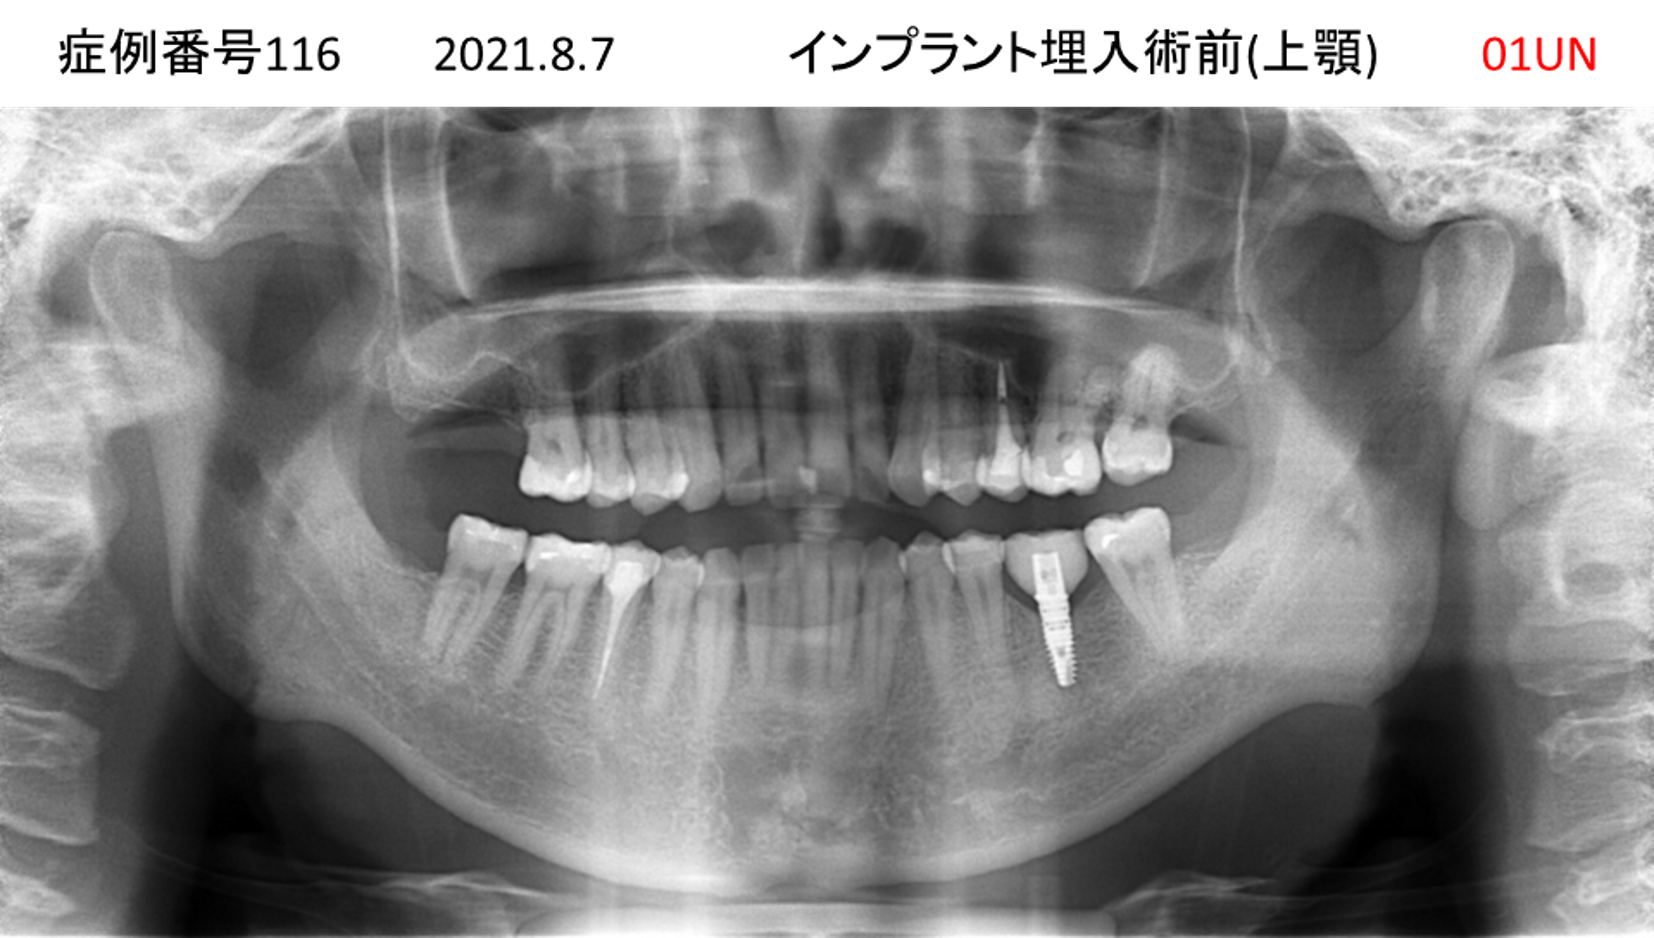

上の前歯が揺れてきてかめない患者様のインプラント症例

| 治療名称 |

インプラント |

| 治療費用 |

440万円+税 |

| 治療期間 |

6か月 |

| 患者さんの症状(主訴) |

上の前歯が揺れてきた。かめない |

| 治療内容 |

サイナスリフト、GBR、インプラント、即時荷重 |

| 治療結果 |

上の前歯の揺れが収まった。奥歯でしっかり噛める。 |

| 治療の注意点(リスク/副作用) |

インプラントが壊れたら再治療が必要 |